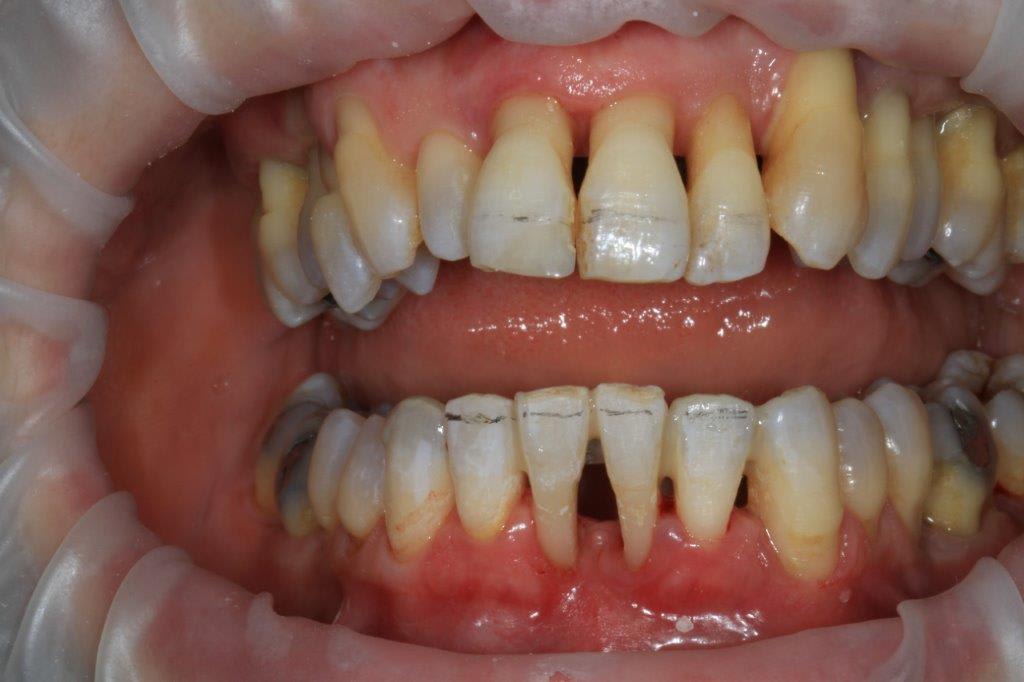

un peu de grain à moudre, toutes les critiques sont les bienvenues...

1ere séance,"nettoyage...", et après réflexion, plutôt que le nettoyage par le vide, attelle de contention pour le bloc antérieur mandibulaire, suppression de quelques contact très parasite sur les pm et canines, et réduction des incisives mandibulaire puis maxillaire... consignes de brossages / bain de bouche avec .... l'érythritol afin de ne pas mourir idiot... on verra ce que ça donne dans un cas relativement perdu d'avance.... merci Algi... enfin peut être : -))

C est dommage que l'on ne voit pas les dents en occlusion .

La 12 est en occlusion inverse et le secteur postérieur 20/30 aussi ?

Une fois de plus ce n est pas un pb Paro mais bien occlusal .

effectivement, je vois la conséquence paro d'un problème avec départ occlusal, mais peut être pas que.